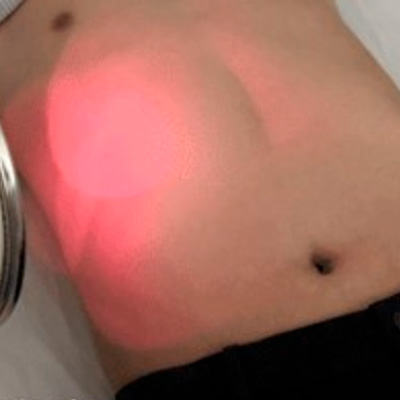

➃ 体表面照射

特定の波長を有したレーザーを体表面照射することで、がん細胞に集積した薬剤に反応させます。その結果、薬剤は発熱し、がん細胞を攻撃します。体表面照射を数回繰り返す事で、がん細胞を死滅させていきます。